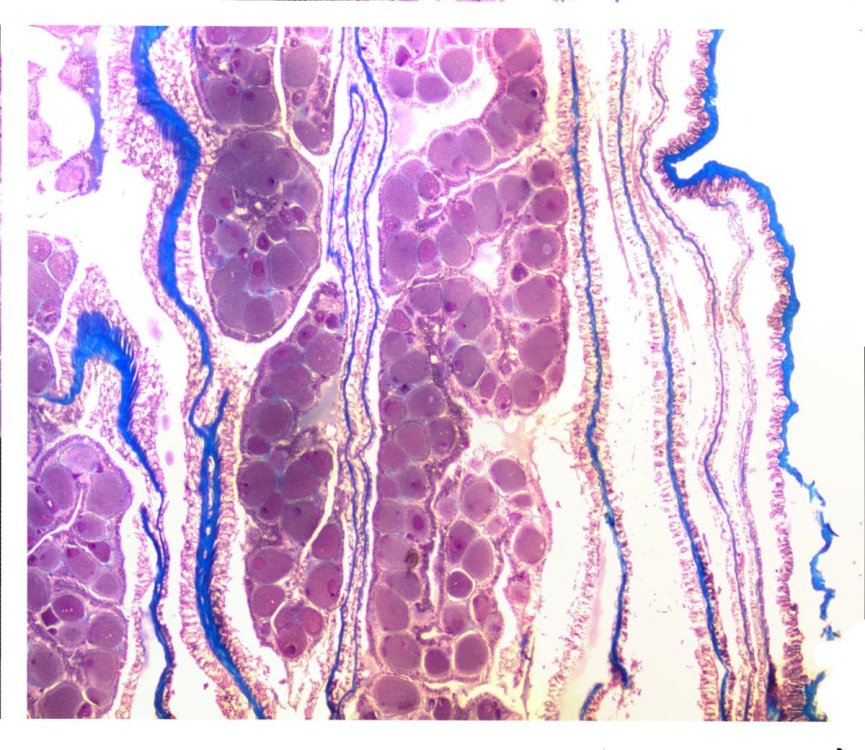

Taenia Saginata (Coupe longitudinale)

Taenia Saginata Un de mes patients se présente à la consultation avec un verre à moutarde contenant un long cordon blanc (il apparaît jaune dans cette observation en raison de la mise dans le Bouin pour la conservation qui colore en jaune le prélèvement). Quelques jours avant il était venu pour se plaindre de curieuses sensations qu’ il percevait à l’ anus et de fragments blancs dans ses sous-vêtements .Le diagnostic n’était pas difficile devant ces symptômes .L’ infestation par un tænia était indiscutable Il lui a été prescrit la prise de 4 cp de Tredémine ( Niclosamine ) ( A noter que les anneaux du ver sont animés de mouvements actifs qui lui permettent un passage vers l’ extérieur pour pouvoir libérer les œufs contenus dans cet anneau dans le sol .). Image de la succession des anneaux ;- dans cette observation on se trouve seulement devant un fragment du ténia ( la tête n’ a pas été trouvée et la taille de ce fragment ne fait que 1metre 20) . Ce long ruban est le résultat de la succession d’anneaux ou proglottis Pour le teania Saginata on compte entre 1000 et 2000 proglottis soit une longueur allant de 5 m à selon certaines publication 25 m. Le proglottis désigne et nomme chacun des anneaux d'un cestode. On parle du proglottide d'un ver annélide quand on parle de la partie située derrière la tête ( le scolex ) du ver qui contient les organes de reproduction mâles et femelles. Les proglottis eux se forment par bourgeonnement en arrière du proglottide. Le scolex est la tête des Cestodes dépourvue de bouche, sans tube digestif ni organes sensoriels, mais portant des ventouses T saginata ( ou avec en plus des crochets T Solium ) pour la fixation. Le revêtement corporel est une cuticule résistante, à travers laquelle la nourriture est absorbée. Photo de la transition entre deux proglottis. Après préparation un proglottis est inclus dans la paraffine et coupé au microtome (coupe de 7 µm ). Coloration Hématoxyline puis Éosine. Coupe tangentielle au plan de l’anneau : Coupe longitudinale Organisation des œufs: sur la coupe longitudinale: Il a été compté autour de 100 000 œufs par proglottis Aspect des œufs Une coque externe, rarement présente, mince, incolore et albumineuse ; Une coque interne qui délimite l'embryophore; c'est l'œuf de Tænia tel qu'on peut le voir habituellement : Taille : 30 µm. Forme : arrondie ; légèrement ovalaire. Couleur : brun foncé. Coque : lisse, très épaisse (4 à 5 µm), striée sur sa largeur. Contenu : embryon hexacanthe avec les six crochets. ( ici difficile à voir ). Image d’une coupe du parenchyme de l’ anneau et de la couche épithéliale : ( : la cuticule ) - Les aliments issus de la digestion de l’ hôte sont dégradés dans l’ intestin grêle , les nutriments passent alors au travers de cette cuticule du tænia. . *************************** Histoire naturelle du tænia ( texte extrait de wikipedia ref 1 ): NB Une oncosphère est la forme larvaire d'un Eucestoda (sous-classe des Cestodes) une fois qu'il a été ingéré par un hôte intermédiaire. Elle est aussi appelée coracidium ou embryon hexacanthe (soit un embryon avec 6 crochets) ou encore simplement hexacanthe1 **************************** Le cycle des ténias est simple. Arrivés dans le milieu extérieur, les anneaux finissent par se désagréger et chacun d'eux libère des milliers d'œufs qui sont disséminés sur le sol et les herbes, ou qui sont transportés par les mains sales (défaut d'hygiène chez l'homme).aprés avoir manipulé du foin Tel était autrefois le cycle naturel quand le tout à l’ égout et les WC n’ était pas répandus - le seau hygiénique était vidé sur le tas de fumier et le fumier étalé dans les prairies Mais aujourdhui les boues des centres d’ épuration des eaux usées se retrouvent aussi dans les champs surtout les champs de grande culture et moins sur les prairies ce qui explique que le taenia saginita est devenu beaucoup plus rare à notre époque Le teania solium a lui quasiment disparu en raison de l’élevage industriel des porcs et de la surveillance vétérinaire des viandes Avalés par un hôte intermédiaire adéquat (bœuf, porc), les œufs donnent des embryons hexacanthes (possédant 6 crochets, comme tous les embryons de cestodes). Ces embryons perforent le tube digestif de l'hôte intermédiaire, passent dans le système circulatoire, et vont se loger principalement dans le muscle ou le tissu adipeux autour des muscles. L'embryon grossit, forme une vésicule et bourgeonne donnant un scolex (tête de ténia) qui reste dans la vésicule, c'est la larve cysticerque. Ces larves sont plus fréquentes chez le bœuf dans les muscles des cuisses, chez le porc dans la langue et le cœur. L'état de l'hôte intermédiaire ainsi atteint est appelé cysticercose, celle du porc est appelée vulgairement ladrerie (porc ladre). Le cysticerque devient mûr et infestant en quelques semaines ou mois. L'homme devient hôte définitif en consommant cette viande crue ou pas assez cuite. Le scolex se libère dans le tube digestif, se fixe à la muqueuse de l'intestin grêle donc possiblement dès la sortie de l’estomac et forme ses anneaux. (proglottis) Il devient adulte en 2 à 3 mois pour libérer les proglottis matures remplis d'œufs. La cysticercose Cette maladie humaine survient lorsque l'homme ingère directement des œufs de ténia (il s'agit presque toujours du ténia du porc Taenia solium exceptionnellement du au teanian saginata) Cela peut se produire par les mains sales en situation d'hygiène précaire, défécation en plein air, utilisation d'engrais humains avec consommation de salades et légumes crus mal lavés, Une autre façon de se contaminer est celle où un patient vomit ou tente de vomir une partie de son ténia. Des anneaux pleins d'œufs peuvent se retrouver dans l'estomac, les embryons sont libérés par le suc gastrique, dans cette situation le sujet est à la fois hôte définitif (pour le ténia) et en impasse parasitaire (pour les cysticerques). Les œufs ainsi ingérés donnent des cysticerques qui se logent préférentiellement dans les muscles, le tissu sous-cutané, l'œil et le système nerveux central. Selon l'OMS, le nombre total de cas de neurocysticercose est estimé entre 2,5 et 8,3 millions de personnes. La cysticercose à T. solium serait responsable de 30 % des épilepsies des régions d'endémie (population en contact avec des porcs errants). En 2000, c'est la première cause d'épilepsie à La Réunion, Madagascar et au Pérou1. Clinique: La présence de ténia adulte dans l'intestin donne des troubles variés, le plus souvent minimes. Ces troubles sont non spécifiques : troubles de l'appétit (boulimie ou anorexie), vagues douleurs abdominales, nausées, troubles du transit (diarrhée ou constipation) de survenue variable et d'évolution déroutante. Ils seraient plus accusés lors de la phase de maturation du ver (les trois premiers mois qui suivent l'infestation). Des troubles seraient plus particuliers à l'enfant comme les troubles neuropsychiques (céphalées, cauchemars, irritabilité...) surtout avec un autre teania Hymenolepis nana. D'autres troubles ont été décrits : cardiovasculaires et respiratoires, troubles cutanés (urticaire, prurit...), etc. L'origine de ces derniers troubles reste discutée (s'ils sont imputables ou non à la présence d'un ténia. Dans la situation la plus fréquente, lorsque le ver est arrivé à maturité, il est bien toléré avec absence totale de symptômes. Le Taenia saginata peut vivre 20 ans. En France on ne rencontre plus que le Taenia saginata ( bœuf ) et quasiment plus le tænia du porc ( Taneia Solium) ) . La congélation industrielle atteint des températures suffisantes pour tuer les cysticerques, mais pas les congélateurs familiaux. Traitement Des médicaments antiparasitaires (vermifuges) sont généralement prescrits pour le tuer. Les molécules les plus connues sont la niclosamide, l'ivermectine et le praziquantel. La surveillance du traitement se fait sur la disparition des symptômes, l'arrêt d'émission d'anneaux, ou l'élimination du ver adulte dans les selles. Le ver, alors mort, mesure entre 4 et 10 mètres. Seule l'évacuation de la tête, souvent en dernier et avec résistance, indique l'élimination complète du ver, laquelle a généralement lieu en une seule fois mais peut durer plusieurs heures. La prophylaxie repose sur la viande et poisson bien cuits (cuits à cœur). L'éducation sanitaire est essentielle (hygiène alimentaire, personnelle et des toilettes). Il est nécessaire de bien cuire les steak hachés que l’ on a tendance à manger rouge ( j’ ai attrapé un ténia avec un steaks du restaurant Universitaire ) A noter qu’il existe d’autres espèces de ténias mais pas en France Référence https://fr.wikipedia.org/wiki/T%C3%A9nia https://mavink.com/explore/Taenia-Solium-Part https://devsante.org/articles/reconnaitre-les-oeufs-de-cestodes-dans-les-selles/ Dominique.